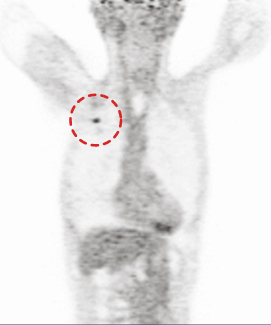

CASE #1 [lung cancer]

15 min (50%) Scan without Denoising

15 min (50%) Scan With Denoising

30 min (100%) Scan Standard